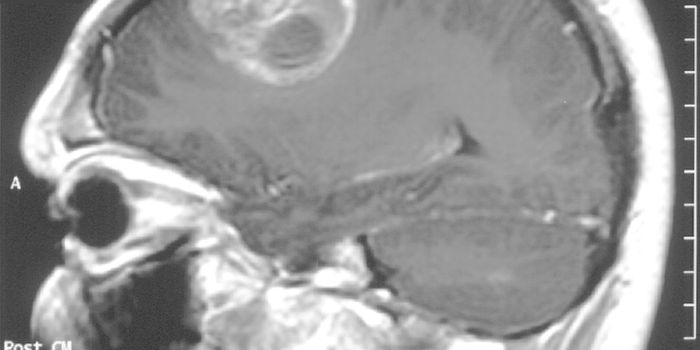

MAR 20, 2019VideosA 31-year-old British man had to go to the hospital after getting an infection in his ear that spread to the lining of h ...